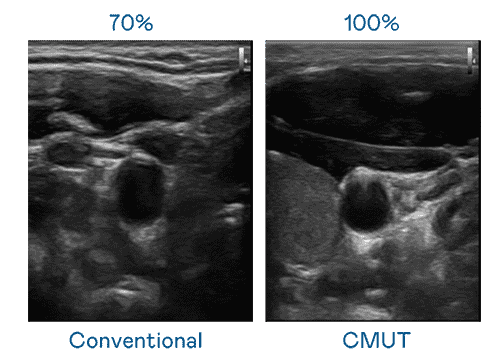

CMUT 技术是一种用电容式微机电元件来产生超音波讯号的技术。。与传统 PZT 压电式技术相比,,,,CMUT 频宽增加 30%,,更宽频的超音波讯号让影像解析度大幅提升,,是实现高影像品质医疗超音波扫描、、、、促进精准医疗发展的关键技术。。

超音波影像的解析度高低,,,首先取决于探头能发出的讯号频宽。。。糖果派对 CMUT 可提供高清晰的超音波讯号,,,,提供高频宽、、、、高灵敏度、、影像纹理细节更高的超音波影像,,,,协助医护人员缩短影像判读时间及利用精准的医疗影像进行诊断。。。